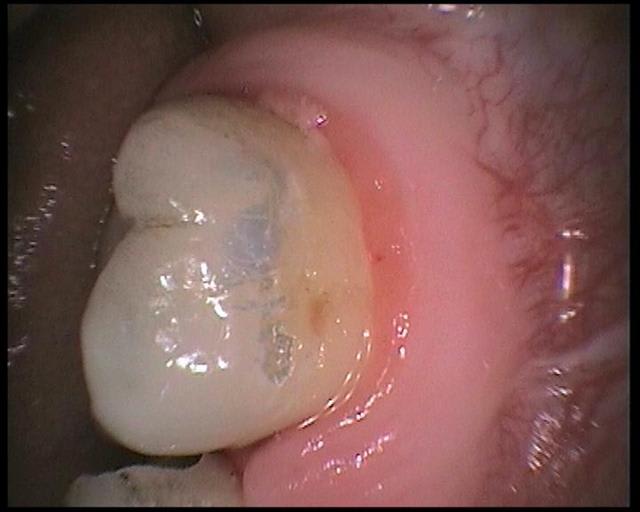

voici les images prises avec la sopro 595

Images en vrac de sopro 595

J'avais eu mon cadeau un peu en avance; cela fait deux mois que je joue avec ma caméra, comme tu peux le voir...